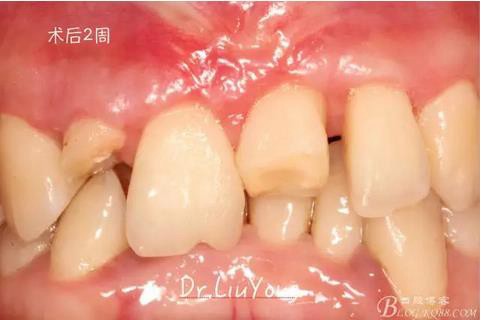

術(shù)后兩周,復(fù)查,A1達(dá)到了完全的根面覆蓋,B1牙齦退縮由原來(lái)的3.5mm減少到1mm,B2近中牙齦也得到部分的恢復(fù),同時(shí)所有牙齦邊緣都通過(guò)手術(shù)增厚。如上圖